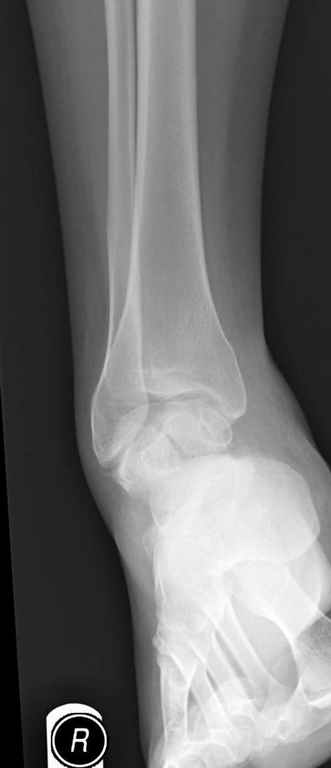

Уважаемые участники русского Ортофорума, поздравляю всех со всеми прошедшими праздниками: Новым годом, Рождеством, Hanukkah, Kwanzaa, желаю участникам всего наилучшего и здоровья.Повреждение таранной кости.Больной 81г автоавария, повреждение таранной кости, здесь снимки.

Какие рекомендации?Djoldas Kuldjanov, MDDepartment of Orthopedic SurgerySt. Louis University Medical Center